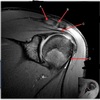

1

Q

What is letter A?

A

SUPRASPINATUS TENDON

What is letter B?

ACROMION

3

CORACOID PROCESS

How well did you know this?